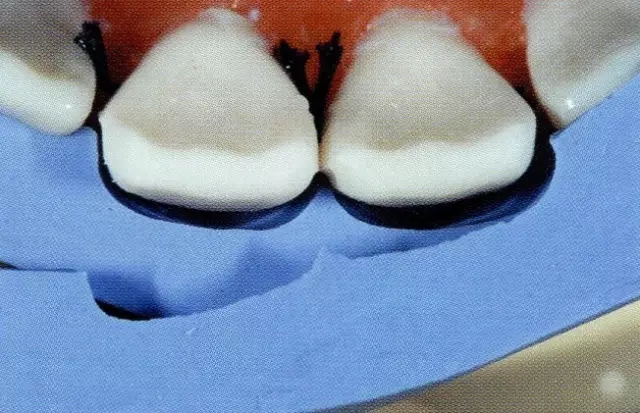

圖9唇側(cè)牙頸部預(yù)備量的確認(rèn)。用硅橡膠印模確認(rèn)預(yù)備量。(約0.5mm)

圖10 完成牙體預(yù)備。以讓應(yīng)力分散型對(duì)線角、點(diǎn)角進(jìn)行了圓滑處理。